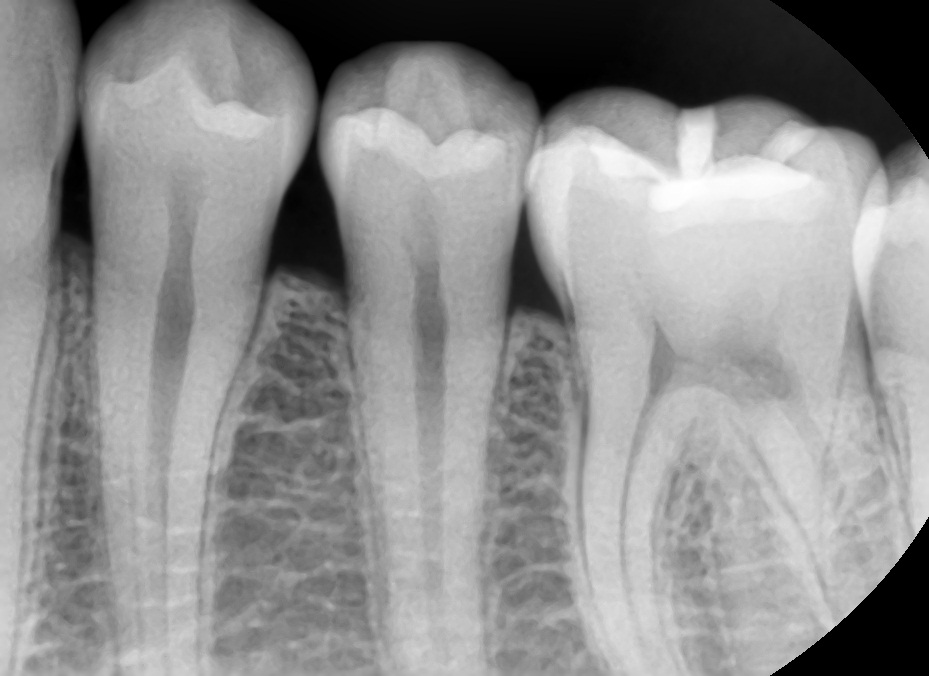

3주만에 충치가 상아질을 뚫을수있나요?

3년간 양치안했더니 법랑질에 국한된 충치가생긴 어리석은 청년입니다. 요즘도게을러서 사진속 치아상태에서 3일에 한번주기로 꼼꼼하게 양치와 치실질을 진행했었는데 3주정도 되었습니다. 3일에 한번씩 꼼꼼하게한정도로는 3주동안 충치가 더 번졌을 가능성이 높나요?

• 2번 째 사진

교합면(씹는면) 충치는 그렇게 빨리 진행되지는 않습니다. 인접면 충치의 경우 법랑질 부위가 얇기 때문에 다소 빨리 진행되는 편은 있지만 3주 내에 급격히 진행되거나 하지는 않습니다. 보통 충치는 만성질환으로 여겨집니다.

단순히 시간적으로 충치가 더 진행된걸 확신할수 없습니다. 관리를 잘하셧다면 3주 안에 충치가 급속도로 진행되진 않습니다.

치근단 사진으로만 확인해 봤을 경우에 상아제 값이 충치가 의심되는 치아가 보이지는 않습니다.

하지만 충치의 여부는 방사선 사진뿐만이 아니라 육안으로도 확인을 해야 알 수 있기 때문에 자세한 확인을 위해서 치과에서 진료를 받아 보세요